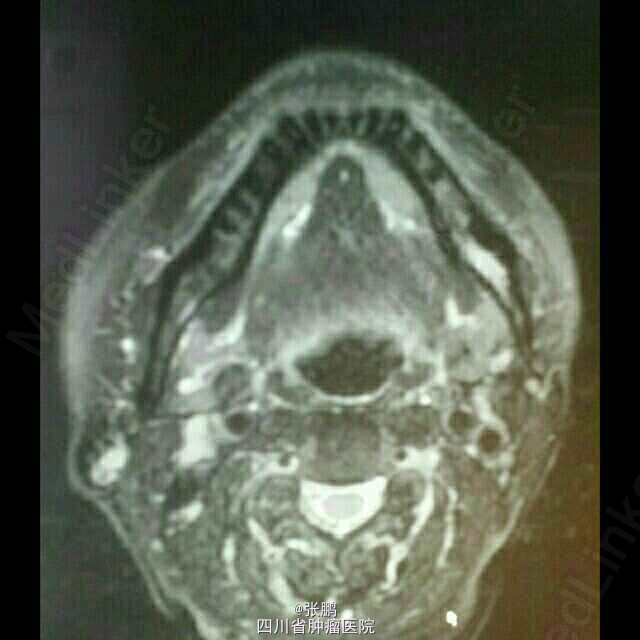

主诉:发现右颞部皮肤肿块9月,活检术后一月。现病史:入院前9月,患者发现右侧颞部包块,无明显疼痛,无流脓渗液,到当地医院就诊,行病灶活检术,病理提示:低分化鳞癌,遂来我院就诊

右侧颞部可见手术切口,长5cm,切口愈合良好

活检术后病例提示:低分化鳞癌。诊断:右侧颞部皮肤低分化鳞癌 采用同步放化疗治疗,化疗方案:吉西他滨+顺铂